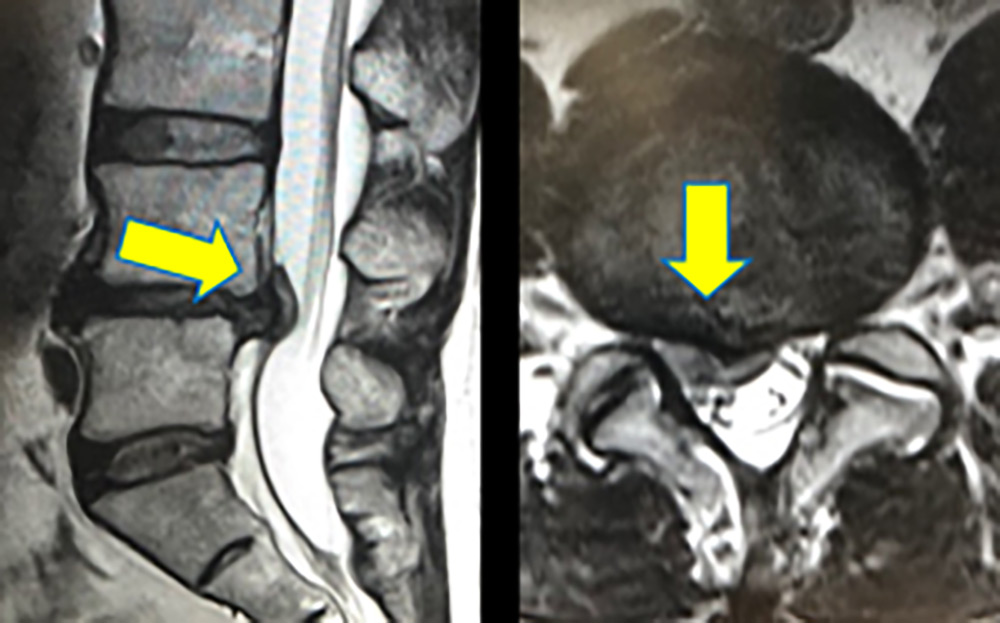

背骨と背骨の間には、クッションの役割を持つ椎間板が存在します。腰の背骨(腰椎)の椎間板が後方に飛び出したものを腰椎椎間板ヘルニアといい、腰痛を伴う事があります。腰椎椎間板ヘルニアが神経を物理的に圧迫すると下肢の痛みを感じ、立ったり座ったり姿勢によって痛みが強くなり、日常生活に支障を来たすようになります(図1)。

腰椎椎間板ヘルニアのMRI像

図1 腰椎椎間板ヘルニアのMRI像